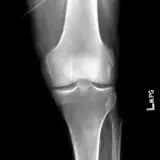

Over 2,100 interactive radiology cases, curated by radiologists for your level of training. Scroll, window, and view cases full screen โ€” just like on PACS. Click linked findings in each writeup to jump straight to them on the image. Cases include sample reports, a focused discussion section, original illustrations, and videos.

Casi completamente interattivi con gli strumenti che ti aspetti su un PACS: scroll, windowing, zoom, pan, misurazioni, ROI e modalitร  a schermo intero.

Annotazioni dettagliate evidenziano i reperti chiave direttamente sui casi. Clicca sui reperti collegati nella descrizione del caso per saltare alla loro esatta posizione sullo scan.